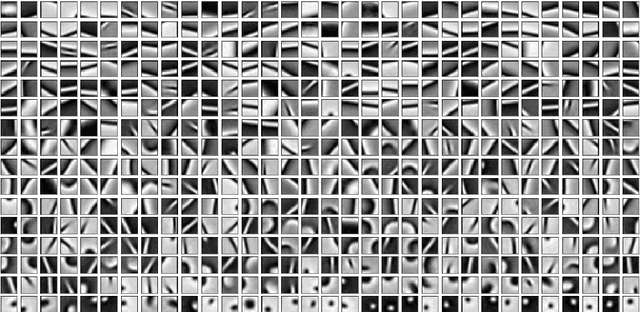

Abstract:This work presents an approach for image reconstruction in clinical low-dose tomography that combines principles from sparse signal processing with ideas from deep learning. First, we describe sparse signal representation in terms of dictionaries from a statistical perspective and interpret dictionary learning as a process of aligning distribution that arises from a generative model with empirical distribution of true signals. As a result we can see that sparse coding with learned dictionaries resembles a specific variational autoencoder, where the decoder is a linear function and the encoder is a sparse coding algorithm. Next, we show that dictionary learning can also benefit from computational advancements introduced in the context of deep learning, such as parallelism and as stochastic optimization. Finally, we show that regularization by dictionaries achieves competitive performance in computed tomography (CT) reconstruction comparing to state-of-the-art model based and data driven approaches.